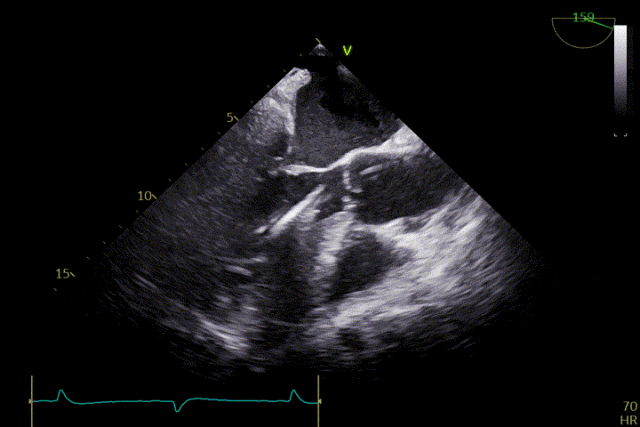

Under echocardiographic guidance, the surgical team efficiently and precisely completed valve positioning, deployment, and functional assessment. The procedure proceeded smoothly: engagement of the graspers into the aortic sinuses and positioning were accomplished in one continuous step. The release and anchoring positions of the three graspers were fully consistent with the preoperative assessment, and device manipulation time was approximately 5 minutes. Intraoperative echocardiography showed no paravalvular leak, and hemodynamic parameters remained stable throughout. The procedure was completed successfully without complications.

Deployment of the positioning device

Advanced into the aortic sinuses